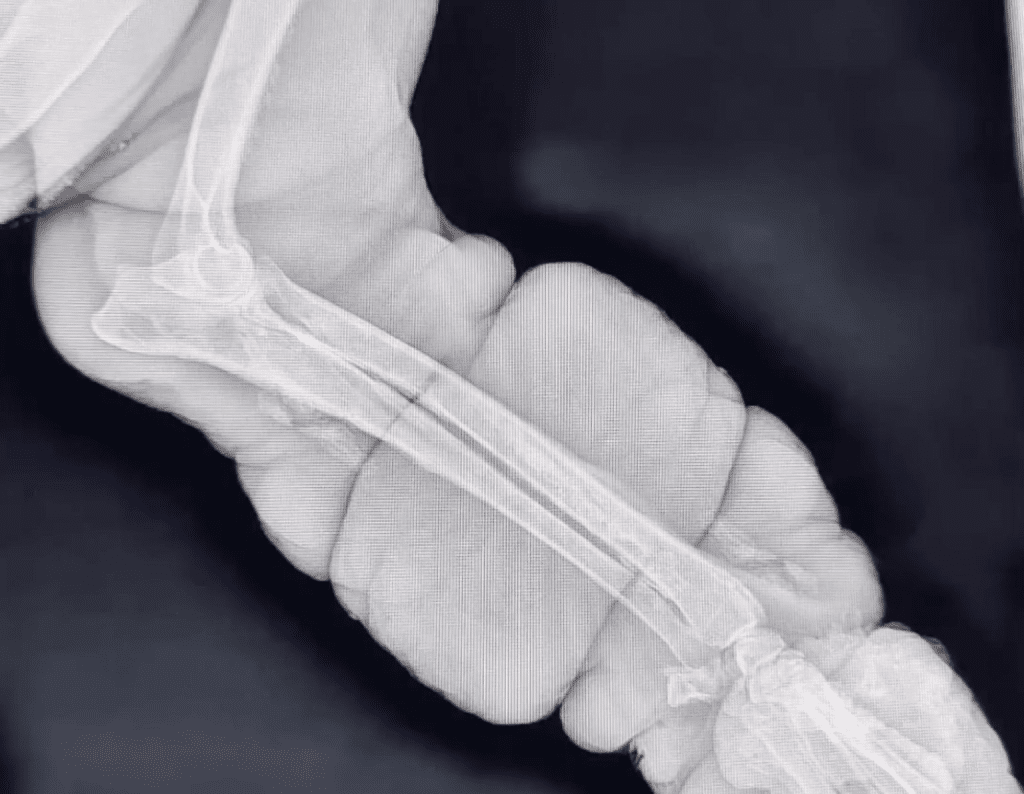

The Answer Hidden in His Pain

The veterinary exam revealed what his body had been trying to endure in silence. X-rays showed a serious bone disease that had been causing Avocado constant pain. Without intervention, it would only worsen. The veterinarian explained the truth carefully: the only path forward—the one that offered him a future without suffering—was surgery.